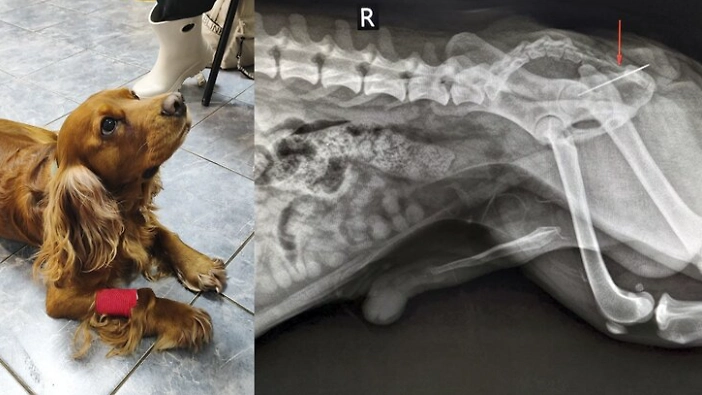

Специалисты ветеринарной клиники в Коптево успешно извлекли швейную иглу, которую проглотил кокер-спаниель по кличке Вольт. Как рассказали в столичной государственной ветеринарной службе, хозяева собаки обратились за помощью, заметив, что питомец испытывает дискомфорт и не может сходить в туалет.

Во время осмотра терапевт обнаружила, что из заднего прохода животного торчит швейная нитка. Рентген подтвердил, что к нитке прикреплена игла, которая беспрепятственно прошла весь желудочно-кишечный тракт и застряла в прямой кишке. Хирург и анестезиолог провели операцию по извлечению инородного тела, после чего собака была отправлена домой.